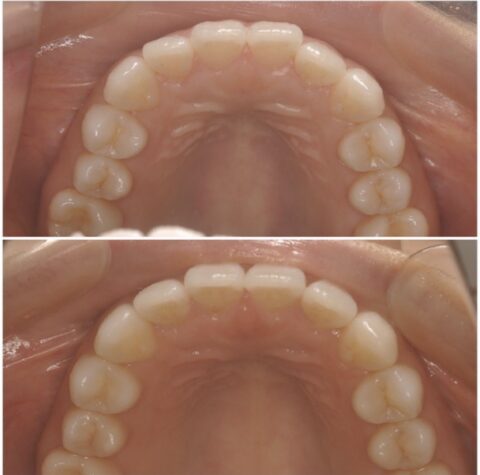

下顎

上顎

上下共に綺麗に並んでいます。